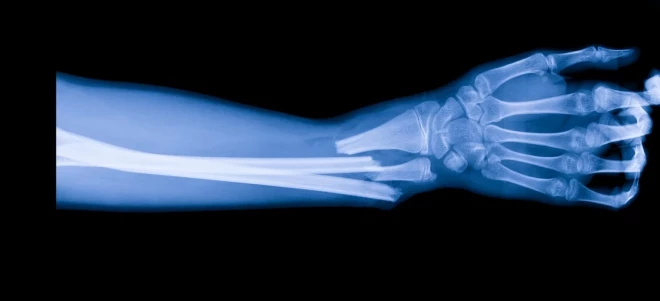

Krītot cilvēki visbiežāk salauž potīšu, pleca un apakšdelma kaulus. Kad kritiena brīdī ir aizņemtas rokas, nokrīt uz pleca, to bojājot. Savukārt, krītot atmuguriski, var salauzt lāpstiņu.

Pirmajās nedēļās pēc lūzuma veidojas lokāls asinsizplūdums, jo tiek bojāts kauls. Divu nedēļu laikā tūska un asinsizplūdums pakāpeniski uzsūcas. Tas var veicināt kaulu lūzumu sekundāru nobīdi. Uzreiz pēc traumas veic rentgenu, vajadzības gadījumā roku vai kāju imobilizē ar ģipsi, un parasti ķirurgs iesaka pēc 7–10 dienām atkārtoti veikt rentgenu, lai pārliecinātos, vai kauls nav nobīdījies. Ja tas notiek, nepieciešama operācija; ideālais laiks operācijai ir pirmās divas nedēļas pēc traumas. Pie ārsta jādodas nekavējoties reizēs, kad saglabājas sūdzības vai situācija pasliktinās, sāpes palielinās. Tādā gadījumā traumatologs var nozīmēt arī datortomogrāfiju vai magnētisko rezonansi, lai lemtu par turpmāko ārstēšanu.